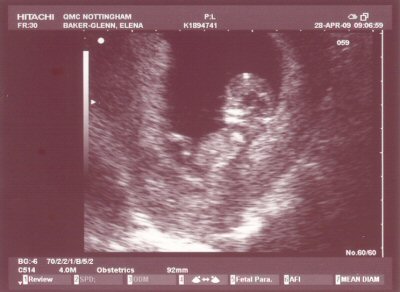

- The scan photo shown below is the dating scan. The due date is 8th November 2009, meaning that the baby was 12 + 2 weeks gestation at the time of the scan. The CRL was 57mm.

- The scan photo shown below was taken at 7 + 4 weeks gestation. The CRL was 7mm.